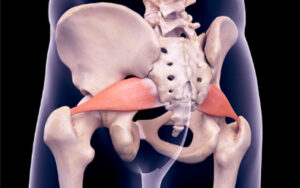

the effects of the upper cervical misalignment

Understanding Atlas Subluxation Complex

Understanding Atlas Subluxation Complex  Table of Contents Toggle What is the Atlas Subluxation Complex?Causes of Atlas Subluxation ComplexHow Atlas Subluxation Complex Affects the BodyThe Role of Chiropractic Care in Correcting…